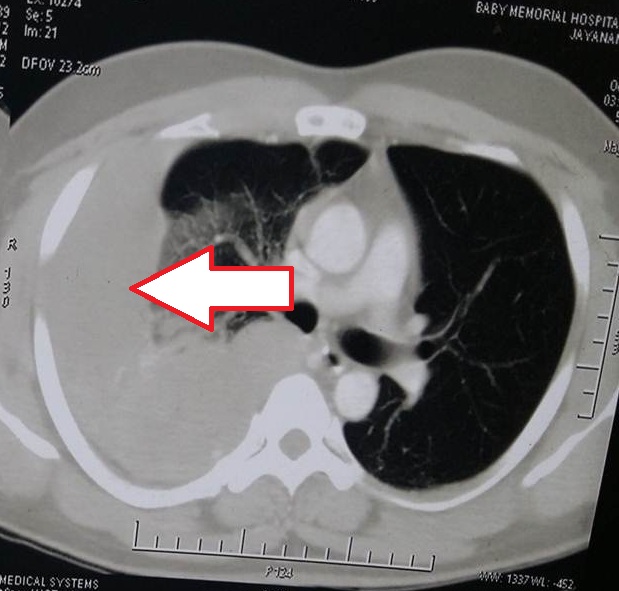

- Figure 3. Right upper lobe mass

- Figure 4. CECT Thorax showing a heterogeneous mass in the posterior aspect of the right upper lobe eroding the rib margin